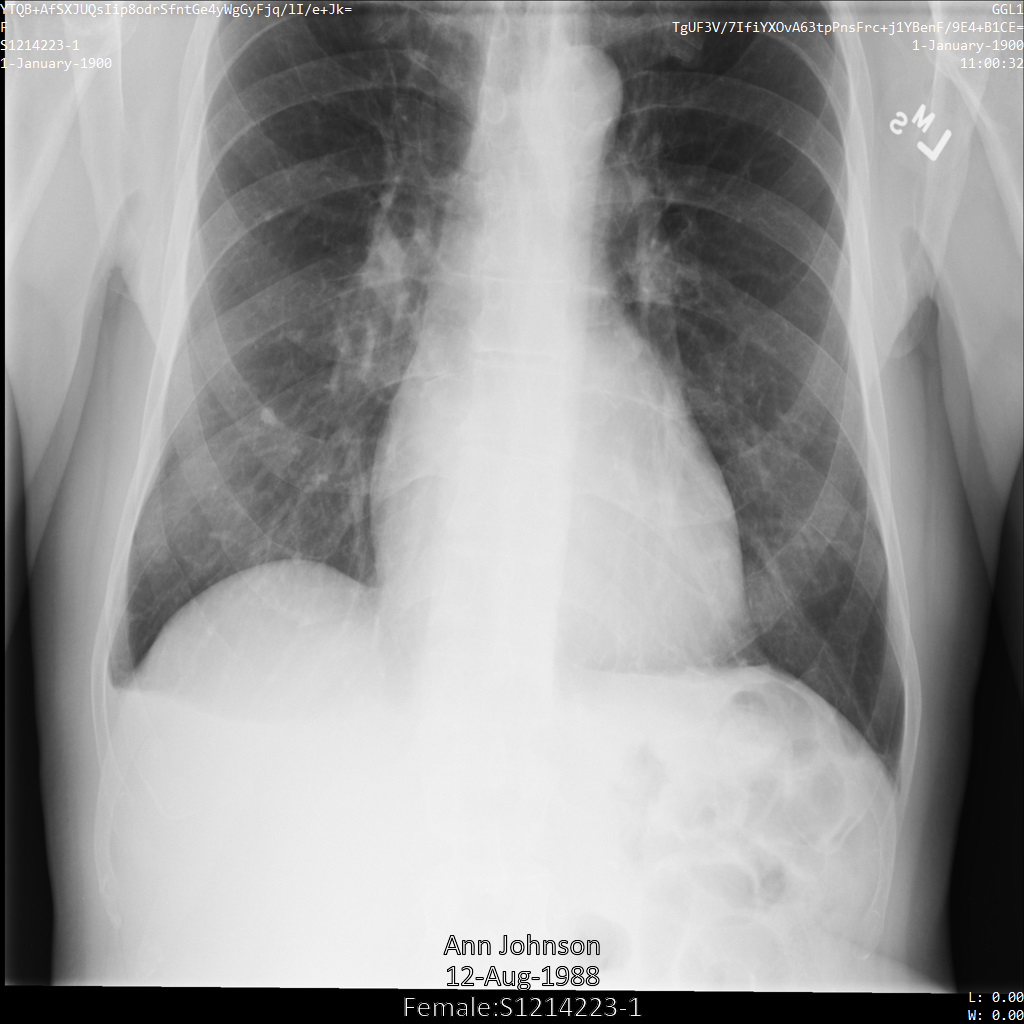

En cada una de las siguientes secciones, se proporcionan ejemplos de cómo desidentificar datos de DICOM mediante varios métodos. Se proporciona un resultado de la imagen desidentificada en cada muestra. En cada muestra, se usa la siguiente imagen original como su entrada:

Puedes comparar la imagen de salida de cada operación de desidentificación con esta imagen original para ver los efectos de la operación.

En la siguiente imagen, se muestra una radiografía sin ocultamiento de un paciente: